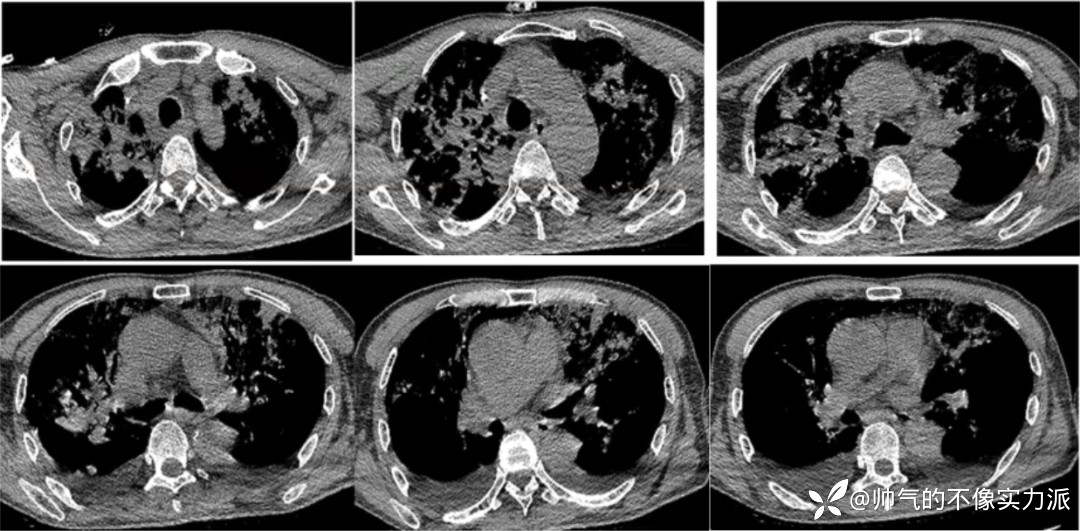

- 复查胸部CT(2020-12-16):双上肺病变仍然较重,双下肺重力依赖区实变影明显吸收,双侧少量胸腔积液(图5)。

图5 患者胸部CT(2020-12-16)

- 2020年12月23日复查胸部CT:双上肺病变明显吸收,遗留少量斑片条索影,双下肺吸收良好(图7)。

图7 患者胸部CT(2020-12-23)